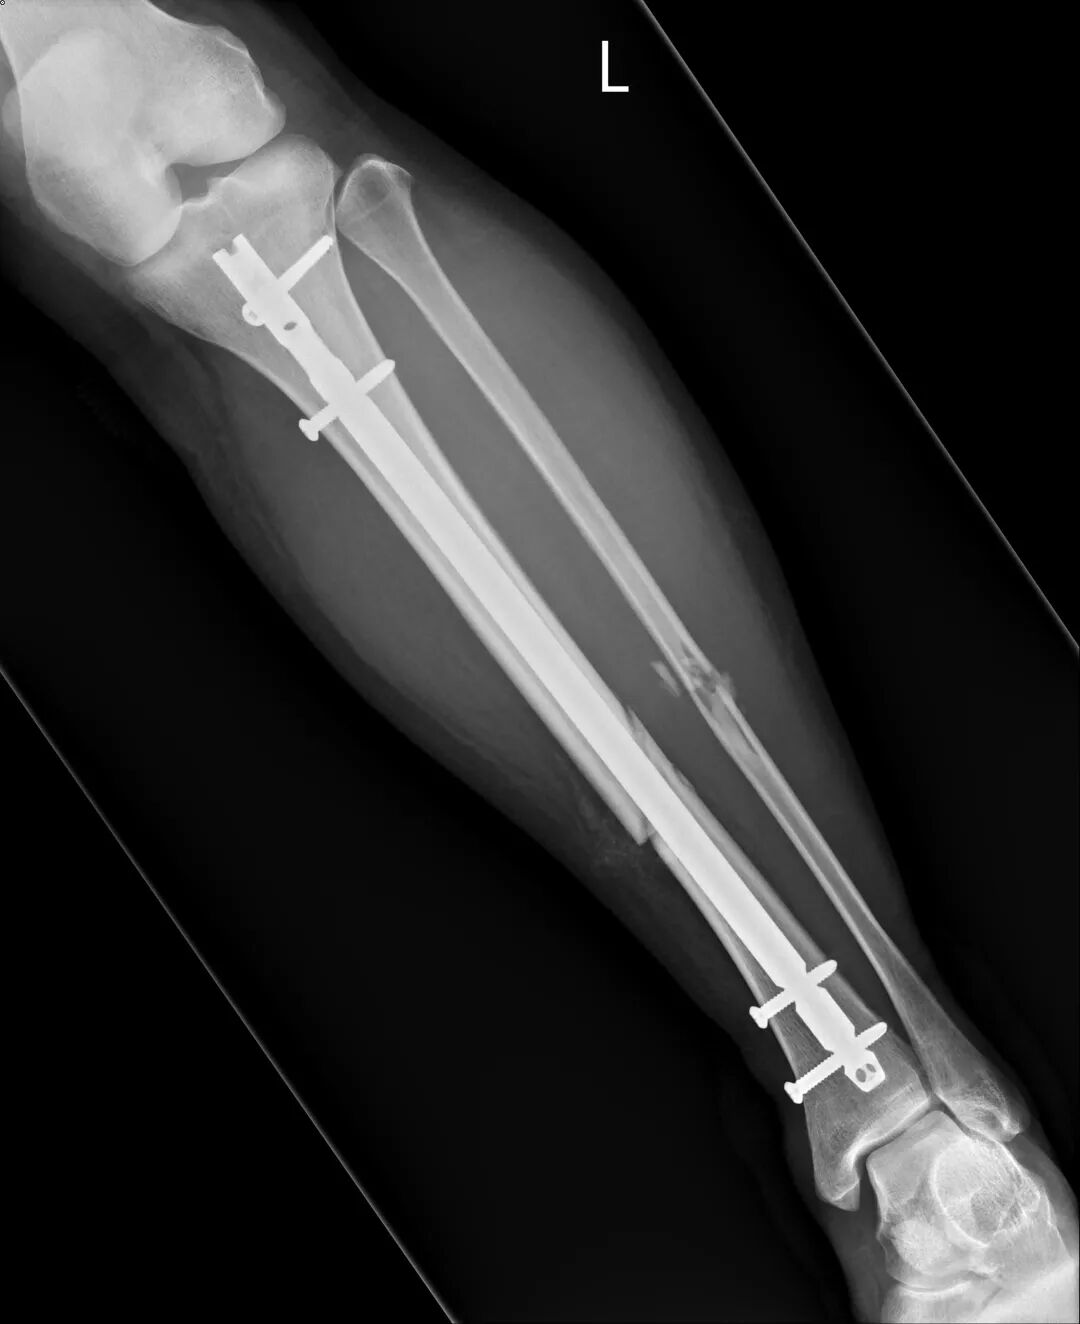

医生告知诊断:小腿里两根骨头都断了,要用手术固定。小腿里有两根骨头,胫骨和腓骨。他们的排列像吃鸡翅时,掰开的那大小骨头。

医生解释手术流程与费用。骨钉有两选择,健保和自费。健保的是不锈钢材质,自费的是钛合金。通常自费医材可拥有较良好的治疗效果。我立即决定用自费医材,商业保险这时候派上用场了。

下午三点,我独自被推去楼下手术房,妈独自留在病房等电话通知。

脑袋变得昏沉,半梦半醒,直到有人呼我的名字,并被把我往手术室。

手术室灯光不太明亮,氛围很轻松,音响播着流行歌曲。我从病床移动到手术台上,瑜伽里的摊尸式(Shavasana)大字型躺着,两手臂放在金属物体上,手术房温很低,没有棉被,我瑟瑟发抖,体温的流逝让意识也跟着越来越模糊。

麻醉师和我确认是选择要全身麻醉后,在我脸上放呼吸面罩,“这只是氧气。”听着静麻醉药物注射数字慢慢上升,我也进入麻醉状态。

“好痛,好痛。”我扭动着身体,喉咙乾涩沙哑地叫着,眼皮重得睁不开。床边有人回应已经帮我注射止痛针了。紧紧抱着怀中释出热风的机器,盼望发挥药效。

手术后几天,我每六小时讨一剂止痛针,想麻痹自己,脱离疼痛。

复健科医生看到X光片后都说:“你这个很严重耶。”为了想尽快恢复生活,我积极去复健治疗。因长时间卧床,受伤腿肌肉严重萎缩,努力运动,抵挡肌肉流失的速度。